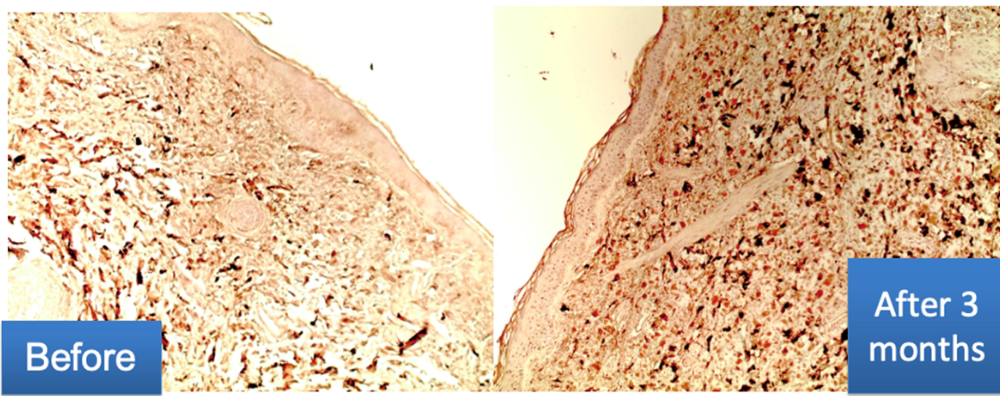

Examen inmunohistoquímico:

- El contenido de colágeno III en la dermis aumenta notablemente

- Formación de fibras orientadas longitudinalmente